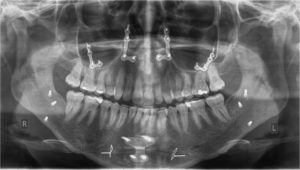

Υλικά οστεοσύνθεσης σε μετεγχειρητική πανοραμική ακτινογραφία περιστατικού ορθογναθικών επεμβάσεων στην άνω γνάθο, στην κάτω γνάθο και στο γένειο.